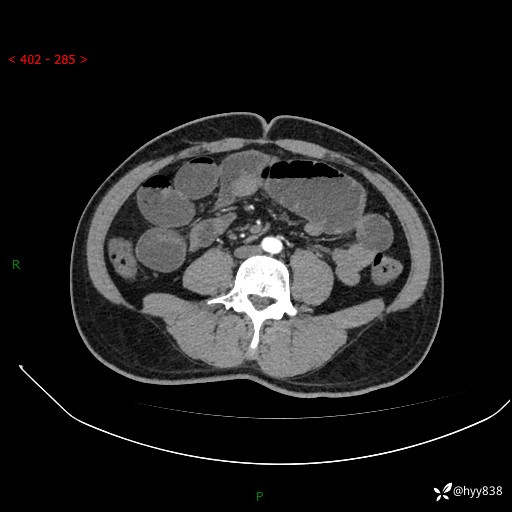

年轻男性,腹痛5月余。除了肠梗阻,你还能看到什么---结果公布~

主诉:腹痛5月余。

现病史:患者于5月前无明显诱因开始出现腹痛,上明显,为间断性胀痛不适,无畏寒发热,无心慌气促等特殊不适,遂来我院。我院门诊遂以“腹痛原因待查”收入我科。 起病以来,患者精神、饮食、睡眠欠佳,大小便正常。体力体重无明显变化。

腹部CT增强扫描(动脉期+静脉期)